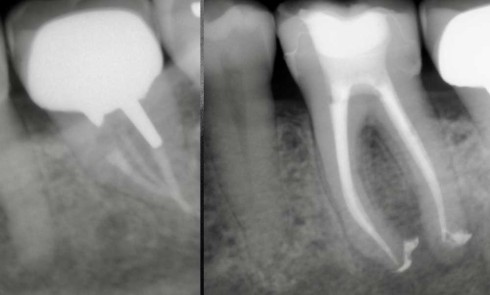

Article réservé à nos abonnés Les douleurs postopératoires sont-elles systématiques en endodontie ?

La gestion de la douleur est un aspect critique de toute pratique endodontique, puisque c’est fréquemment le seul critère d’appréciation...